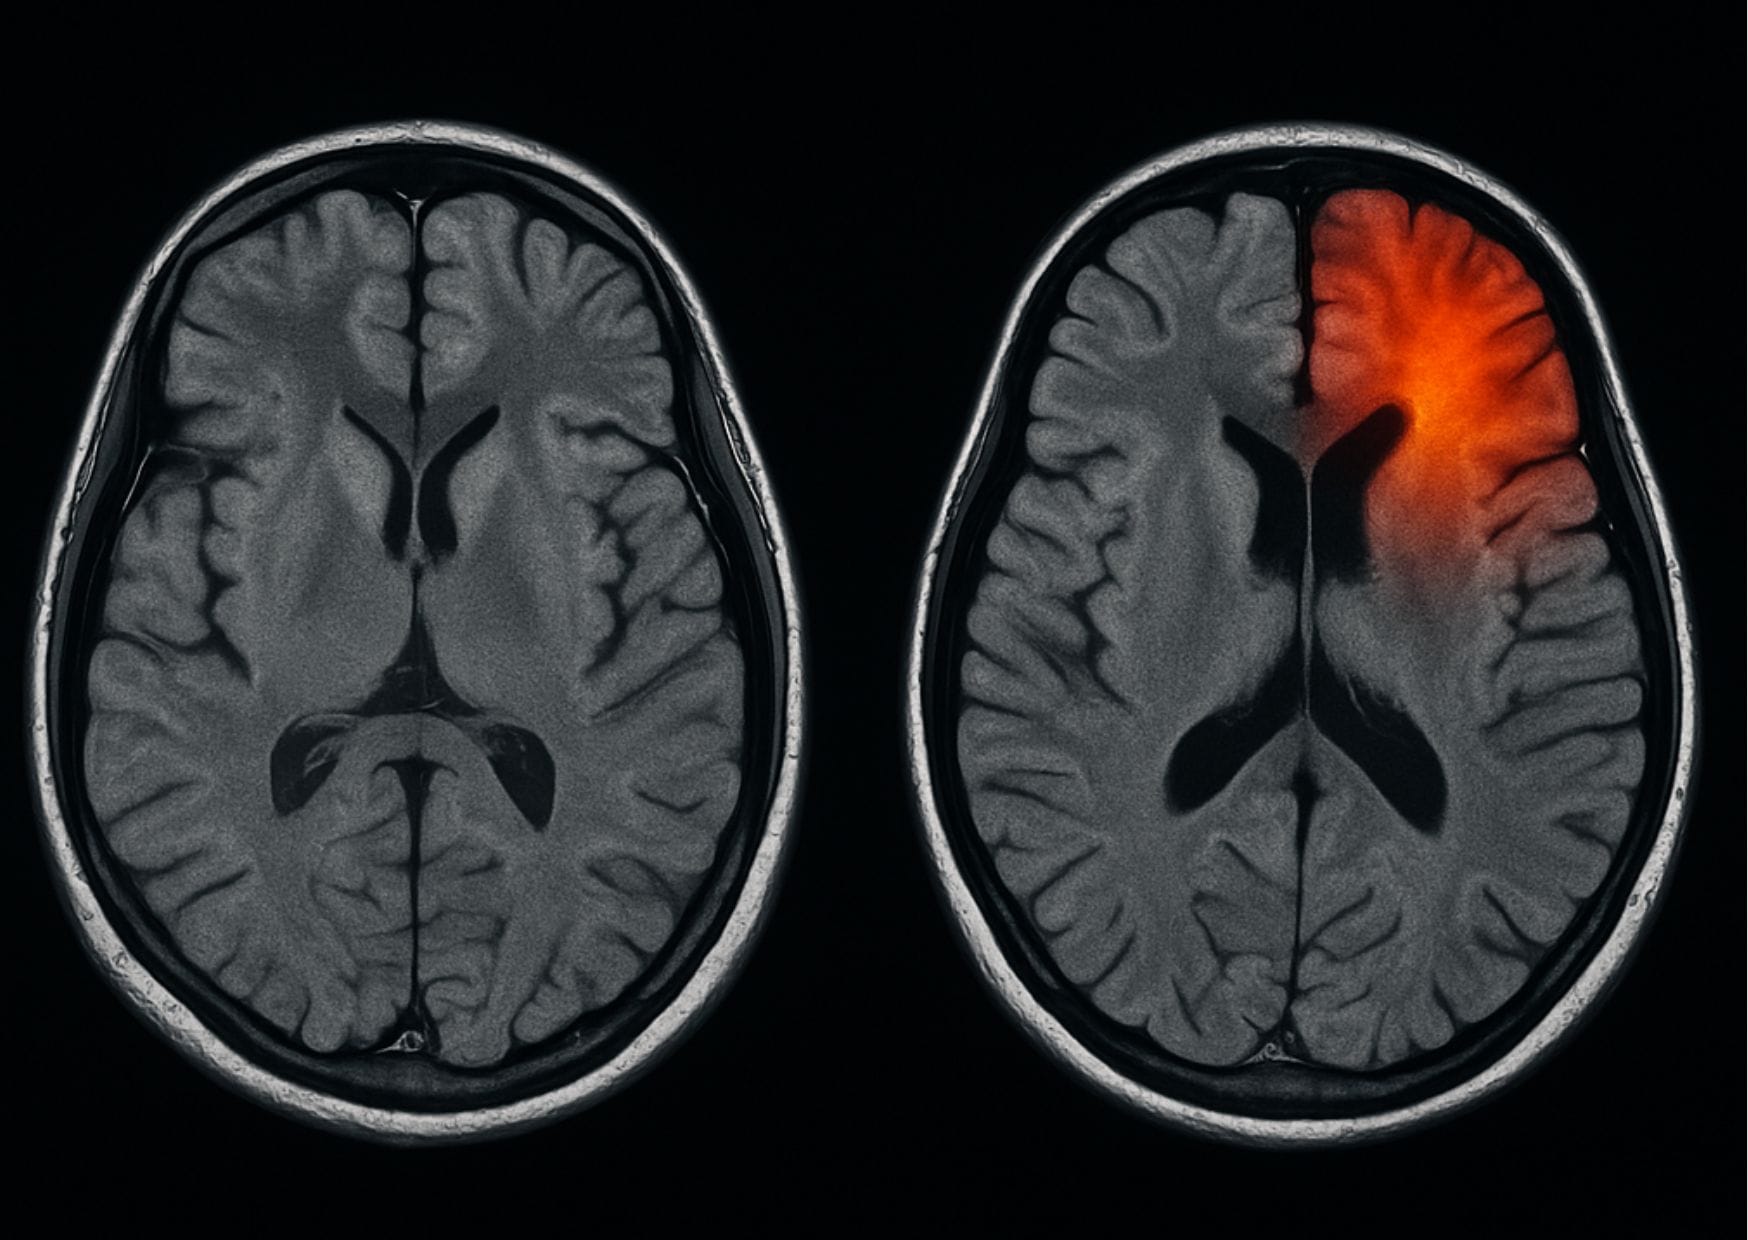

Rehabilitación de un Ictus, causas, síntomas, factores de riesgo La rehabilitación de un ictus es uno de los procesos más importantes para recuperar la independencia y la calidad de vida tras haber sufrido este episodio. Cada 29 de octubre, en el Día Mundial del Ictus, recordamos que actuar a tiempo puede marcar la diferencia, pero…